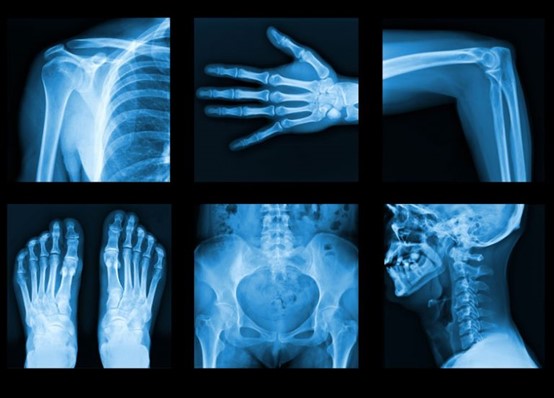

An Article entitled ( X-ray)

X-ray, is a penetrating form of high-energy electromagnetic radiation. Most X-rays have a wavelength ranging from 10 picometers to 10 nanometers, corresponding to frequencies in the range 30 petahertz to 30 exahertz (30×1015 Hz to 30×1018 Hz) and energies in the range 145eV to 124 keV. X-ray wavelengths are shorter than those of UV rays and typically longer than those of gamma rays. In many languages, X-radiation is referred to as Röntgen radiation, after the German scientist Wilhelm Conrad Röntgen, who discovered it on November 8, 1895 He named it X-radiation to signify an unknown type of radiation. X-rays are generated via interactions of the accelerated electrons with electrons of tungsten nuclei within the tube anode. There are two types of X-ray generated: characteristic radiation and bremsstrahlung radiation. <br /> The most familiar uses are: <br /> X-rays can be used to treat tumors in the human body. According to scientists, when the human body is exposed to the right amount of X-rays, this action is capable of destroying certain tumors in the body. Scientists say if this is done very well, the tumors will be destroyed by the X-rays and no harm will be done to the surrounding tissues. Over the years, X-rays have been used extensively to treat people suffering from certain types of tumors. Because of X-rays, doctors are able to easily detect things such as a bone fracture or sprain in the body. This would have been next to impossible in the absence of X-rays. Can you imagine how difficult it would have been for doctors to check for broken bones in the body without the use of X-rays? But thanks to X-rays, these things are now pretty simple.x-rays are not only used in the destruction of malignant tumors, but they are also used by doctors to treat leukemia. Doctors use X-rays to examine the breast to look for breast cancer. X-rays do not only spot cancers, but they can also be used to -stop the growth of cancer cells. The right amount of X-rays introduced to the body can effectively destroy cancer cells growing in the body. X-rays can also be used to photograph the teeth and detect any abnormal growth of teeth. <br /><br /><br />By Elaf Mehdi